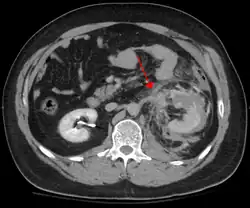

Blunt abdominal trauma

Blunt abdominal trauma (BAT) represents 75% of all blunt trauma and is the most common example of this injury.[3] Seventy-five percent of BAT occurs in motor vehicle crashes,[4] in which rapid deceleration may propel the driver into the steering wheel, dashboard, or seatbelt,[5] causing contusions in less serious cases, or rupture of internal organs from briefly increased intraluminal pressure in the more serious, depending on the force applied. Initially, there may be few indications that serious internal abdominal injury has occurred, making assessment more challenging and requiring a high degree of clinical suspicion.[6]

There are two basic physical mechanisms at play with the potential of injury to intra-abdominal organs: compression and deceleration.[7] The former occurs from a direct blow, such as a punch, or compression against a non-yielding object such as a seat belt or steering column. This force may deform a hollow organ, increasing its intraluminal or internal pressure and possibly leading to rupture.[7]

Deceleration, on the other hand, causes stretching and shearing at the points where mobile contents in the abdomen, like the bowel, are anchored. This can cause tearing of the mesentery of the bowel and injury to the blood vessels that travel within the mesentery. Classic examples of these mechanisms are a hepatic tear along the ligamentum teres and injuries to the renal arteries.[7]

When blunt abdominal trauma is complicated by 'internal injury,' the liver and spleen (see blunt splenic trauma) are most frequently involved, followed by the small intestine.[8]

In most settings, the initial evaluation and stabilization of traumatic injury follows the same general principles of identifying and treating immediately life-threatening injuries. In the US, the American College of Surgeons publishes the Advanced Trauma Life Support guidelines, which provide a step-by-step approach to the initial assessment, stabilization, diagnostic reasoning, and treatment of traumatic injuries that codifies this general principle.[8] The assessment typically begins by ensuring that the subject's airway is open and competent, that breathing is unlabored, and that circulation—i.e. pulses that can be felt—is present. This is sometimes described as the "A, B, C's"—Airway, Breathing, and Circulation—and is the first step in any resuscitation or triage. Then, the history of the accident or injury is amplified with any medical, dietary (timing of last oral intake) and history, from whatever sources that might be available such as family, friends, and previous treating physicians. This method is sometimes given the mnemonic "SAMPLE". The amount of time spent on diagnosis should be minimized and expedited by a combination of clinical assessment and appropriate use of technology,[33] such as diagnostic peritoneal lavage (DPL), or bedside ultrasound examination (FAST)[34] before proceeding to laparotomy if required. If time and the patient's stability permit, a CT examination may be carried out if available.[35] Its advantages include superior definition of the injury, leading to grading of the injury and sometimes the confidence to avoid or postpone surgery. Its disadvantages include the time taken to acquire images, although this gets shorter with each generation of scanners, and the removal of the patient from the immediate view of the emergency or surgical staff. Many providers use the aid of an algorithm such as the ATLS guidelines to determine which images to obtain following the initial assessment. These algorithms take into account the mechanism of injury, physical examination, and patient's vital signs to determine whether patients should have imaging or proceed directly to surgery.[8]